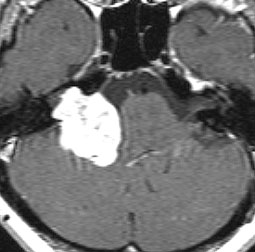

定位分割放射線治療をした聴神経腫瘍の例(左)。20%くらいの確率で放射線治療後に一時的に大きくなることがあります(中央)。やがて小さくなっていきます(右)。放射線治療後に腫瘍が大きくなっても,あわてて手術を受け入れてはいけません。

この画像はMRIのCISS/FIESTA画像というのを用いています。造影剤を使わないでも腫瘍の形と大きさが精密に解るので,経過観察には適している検査法です。

2001年に治療をした,40代女性の大きな聴神経腫瘍です。50グレイ25分割の定位放射線治療を行いました。中央が1年後,右が3年後です。徐々に縮小して手術を必要としませんでした。このサイズの聴神経腫瘍でも放射線治療は選択できるのですが,多くの場合は開頭手術をお勧めするサイズとも言えます。